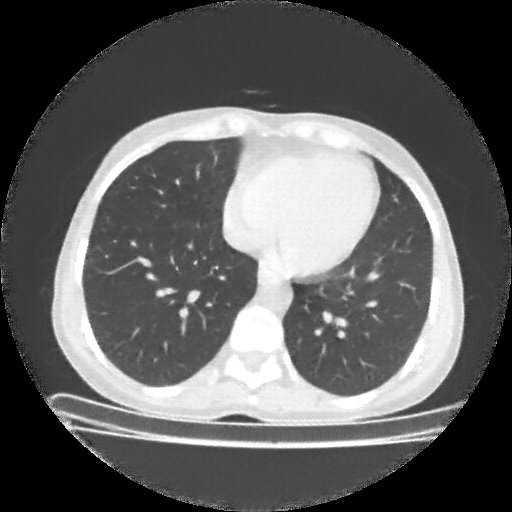

Original NATIVE CT scan (input)

Full window (WL 1023.5, WW 4095 β†’ Low βˆ’1024, High +3071)

Lung window (WL -600, WW 1500 β†’ Low βˆ’1350, High +150)

Mediastinum window (WL 40, WW 400 β†’ Low βˆ’160, High +240)